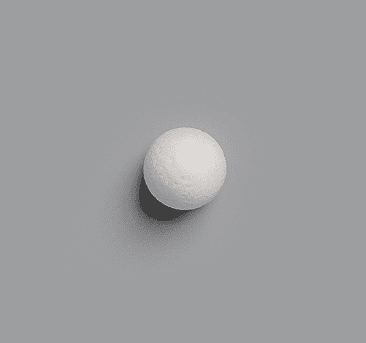

Sphere

Cor-Tec Sphere

Quadro-Port Tunnel Orbital Sphere

Quadro-Port Tunnel Conical Orbital